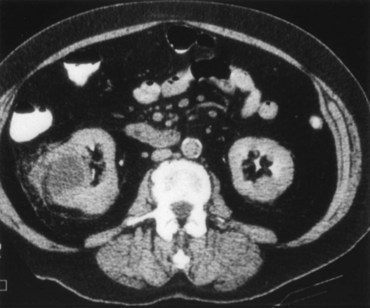

A dedicated (thin-slice) renal CT scan remains the single most important radiographic test for delineating the nature of a renal mass. CT, with and without the administration of contrast material, is necessary to take full advantage of the contrast enhancement characteristics of highly vascular renal parenchymal tumors (Davidson et al, 1997; Zagoria, 2000, Prasad et al, 2008; Ng et al, 2008; Zhang et al, 2007a). In general, any renal mass that enhances with intravenous administration of contrast material on CT by more than 15 Hounsfield units (HU) should be considered an RCC until proved otherwise (Fig. 49–2) (Hartman et al, 2004). Solid masses that also have substantial areas of negative CT attenuation numbers (below −20 HU) indicative of fat are diagnostic of AMLs (Nelson and Sanda, 2002). In 10% to 20% of solid renal masses CT findings are indeterminate, and additional testing or surgical exploration is needed to establish a definitive diagnosis. On occasion, CT demonstrates an enhancing renal segment that is isodense with the remainder of the kidney, suggestive of a renal pseudotumor. Renal pseudotumors may be due to a hypertrophied column of Bertin, renal dysmorphism, or an unusually shaped kidney (Bhatt et al, 2007). In this situation, the diagnosis of a pseudotumor can be confirmed by isotope renography with technetium-labeled dimercaptosuccinic acid or glucoheptonate (Fig. 49–3). These isotope studies demonstrate an area of increased density if the mass is a pseudotumor and an area of decreased density if the mass is a cyst or solid tumor (Israel and Bosniak, 2003a).

Figure 49–2 A, Unenhanced CT scan shows solid, right posterior renal mass. B, After administration of the contrast agent, CT scan shows that the mass enhances more than 20 HU and is thus highly suggestive of RCC. This mass was excised and confirmed to be a clear cell renal cell carcinoma.

(Courtesy of Dr. Terrence Demos, Maywood, IL.)